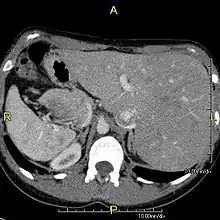

However, in some individuals with PCD, mutations thought to be in the gene coding for the key structural protein left-right dynein (lrd)[8] result in monocilia which do not rotate. There is therefore no flow generated in the node, Shh moves at random within it, and 50% of those affected develop situs inversus, which can occur with or without dextrocardia, where the laterality of the internal organs is the mirror-image of normal. Affected individuals therefore have Kartagener syndrome. This is not the case with some PCD-related genetic mutations: at least 6% of the PCD population have a condition called situs ambiguus or heterotaxy, where organ placement or development is neither typical (situs solitus) nor totally reversed (situs inversus totalis) but is a hybrid of the two. Splenic abnormalities such as polysplenia, asplenia and complex congenital heart defects are more common in individuals with situs ambiguus and PCD, as they are in all individuals with situs ambiguus.[14]

When accompanied by the combination of situs inversus (reversal of the internal organs), chronic sinusitis, and bronchiectasis, it is known as Kartagener syndrome[1] (only 50% of primary ciliary dyskinesia cases include situs inversus).